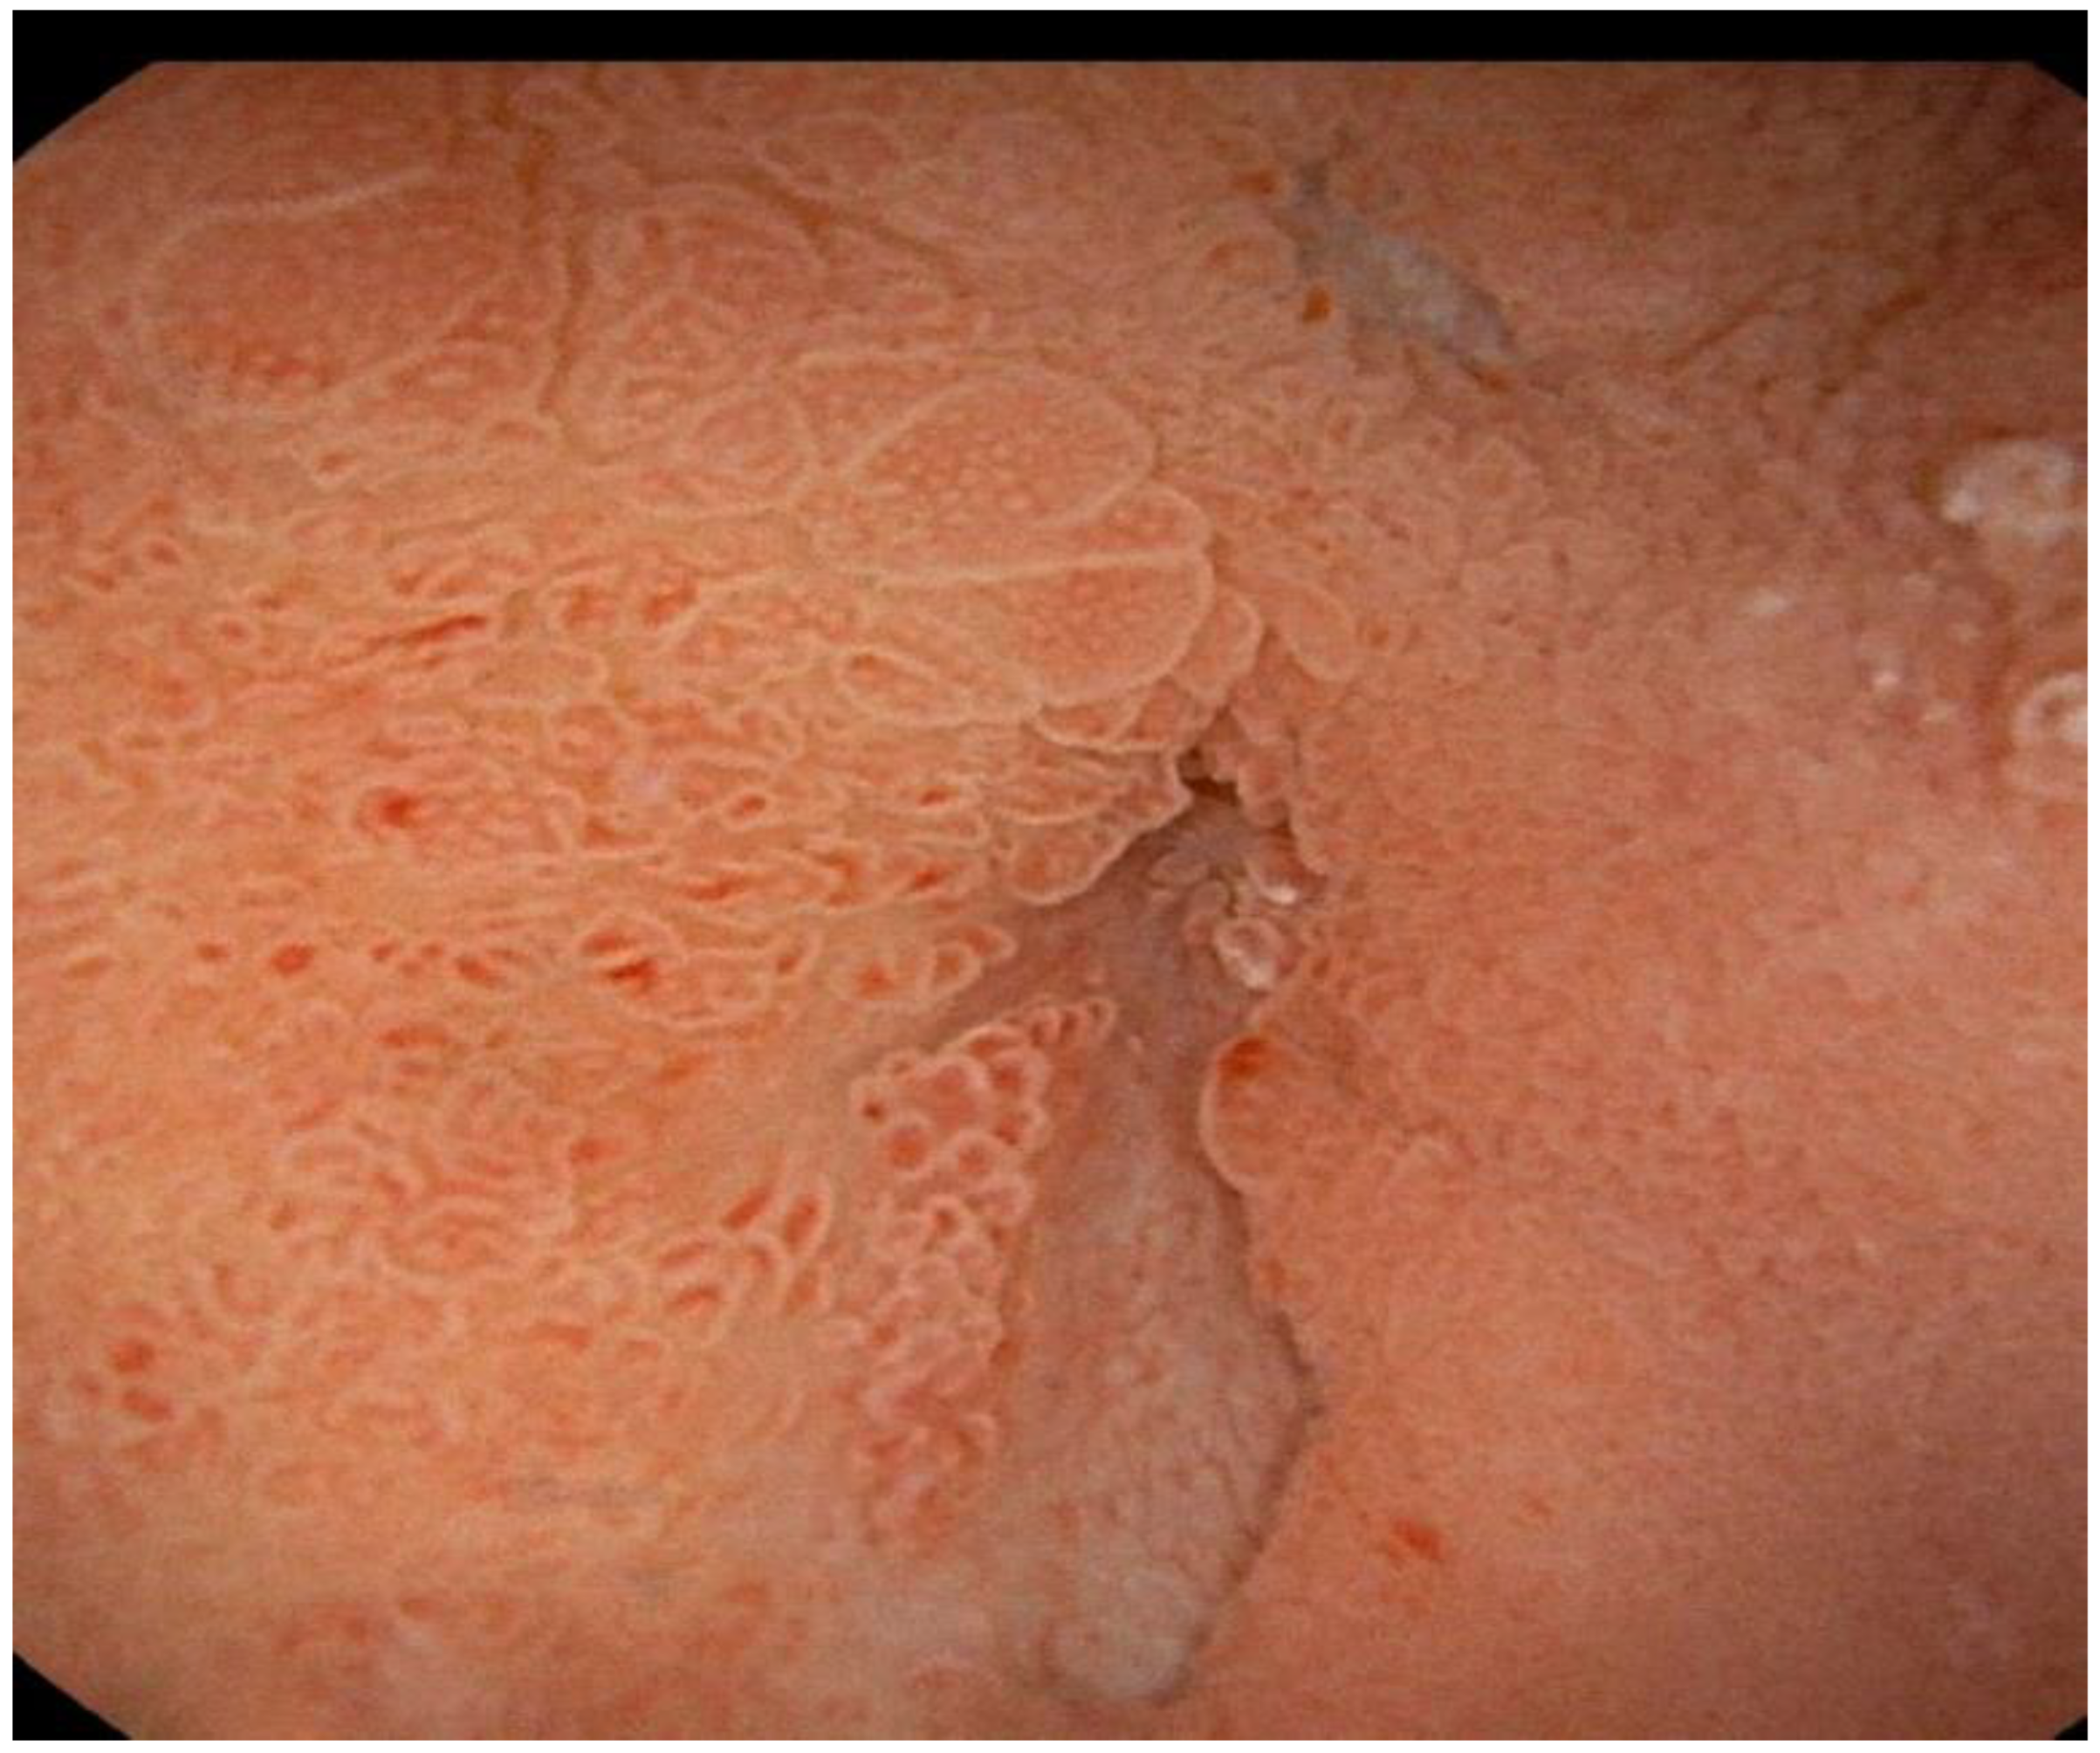

Successful Treatment of Pancreatic Pseudocysto-Duodenum Fistula with Ultrasound Endoscopic Drainage: A Case Report

2. Case Report